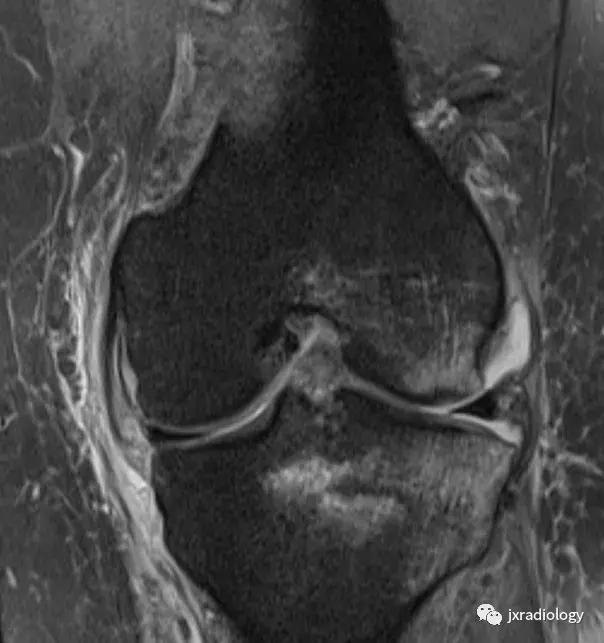

图26:局限性游走性骨质疏松症(具有位置变化的短暂性骨髓水肿综合征)(连续冠状PD-FS-WI):在一些情况下,在连续MRI上看到骨髓水肿的位置变化,这被称为局限性游走性骨质疏松症(RMO);尽管可以自愈的短暂性骨髓水肿综合征的情况更为常见,但可以在一小部分病例中转移到不同的关节,或者(甚至更罕见)转移到同一关节内的不同部位(关节内转移) ,如关于该患者所见。在这个关节内RMO病例中,没有创伤史,水肿始于股骨内侧髁,3个月后发现转移到外侧髁。

图27:废用性骨质疏松症(DO):在骨骺上的所有序列中显示的融合和斑片状中-高信号影是典型的长期固定后的短暂性骨质疏松症。恢复活动在废用骨中产生比在正常骨中更大的应力,因为必须支撑负载的骨小梁更小更弱,因此出现骨髓水肿(应力反应也在内侧髁上看到并用* 标识)。一个愈合的外侧胫骨平台骨折(箭头)。(a-e:PD-FS-WI; f:T1-WI)。值得注意的是,复杂性局部疼痛综合征(CRPS,包括包括反射*交性**感神经营养不良,痛觉神经营养不良和Sudeck骨萎缩)具有与DO相同的MRI骨水肿模式,但其病理生理学与废用脱钙无关,并且总是伴有疼痛(DO是无症状患者的偶然发现,在有外固定的患者中)。

图28:正常的红骨髓:这是寻找骨髓水肿时可能出现的误区。造血系统红骨髓(由于年轻患者正常分布或成人骨髓再生)在T1-WI(b)和水敏序列(a:PD-FS-WI)上均具有中等信号强度。T1-WI上的正常红骨髓相对于肌肉的分布(通常在干骺端)的特征性模式和较高的信号强度(与T1-WI上肌肉组织的等信号或低信号的病理性骨髓相反),应能及时发现这一正常发现。